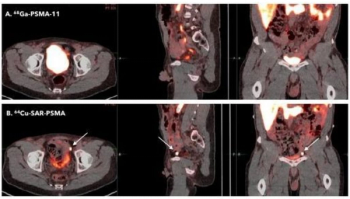

While (68Ga)Ga-PSMA-11 offers a pooled sensitivity rate of 92 percent for prostate cancer, (18F)-based radiotracers may offer enhanced lesion detection as well as improved imaging flexibility, according to a meta-analysis presented at the Society for Nuclear Medicine and Molecular Imaging (SNMMI) conference.